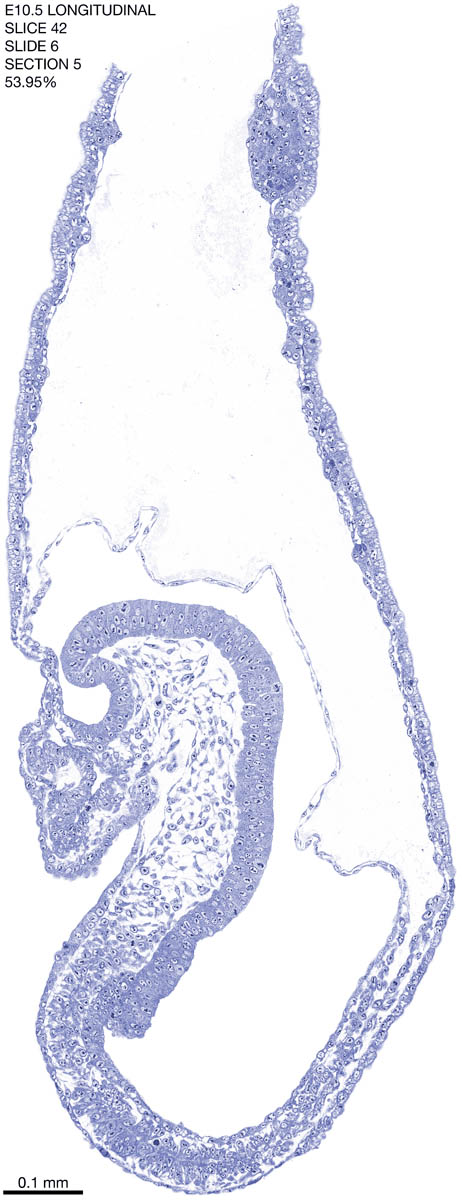

E10.5 Longitudianal Archive This page contains jpg files of ALL SLICES (each 3µm thick) that were scanned of the E10.5 longitudinally cut specimen. Download: Large | High Res Download: Large | High Res Download: Large | High Res Download: Large | High Res Download: Large | High Res Download: Large | High Res Download: Large | High Res Download: Large | High Res Download: Large | High Res Download: Large | High Res Download: Large | High Res Download: Large | High Res Download: Large | High Res Download: Large | High Res Download: Large | High Res Download: Large | High Res Download: Large | High Res Download: Large | High Res Download: Large | High Res Download: Large | High Res Download: Large | High Res Download: Large | High Res Download: Large | High Res Download: Large | High Res Download: Large | High Res Download: Large | High Res Download: Large | High Res Download: Large | High Res Download: Large | High Res Download: Large | High Res Download: Large | High Res Download: Large | High Res Download: Large | High Res Download: Large | High Res Download: Large | High Res Download: Large | High Res Download: Large | High Res Download: Large | High Res Download: Large | High Res Download: Large | High Res Download: Large | High Res Download: Large | High Res Download: Large | High Res Download: Large | High Res Download: Large | High Res Download: Large | High Res Download: Large | High Res Download: Large | High Res Download: Large | High Res Download: Large | High Res Download: Large | High Res Download: Large | High Res Download: Large | High Res Download: Large | High Res Download: Large | High Res Download: Large | High Res Download: Large | High Res Download: Large | High Res